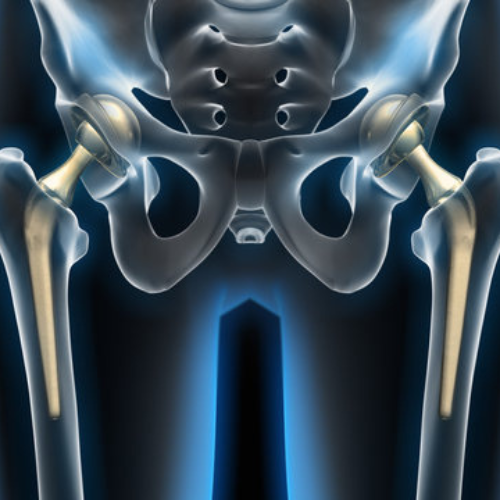

Arthroplasty is a surgical procedure that involves replacing a damaged joint with an artificial implant to restore mobility and eliminate pain. It is most commonly performed on weight-bearing joints like the knee, hip, and shoulder, especially when conservative treatments fail to provide relief.

• Total Hip Replacement (THR)